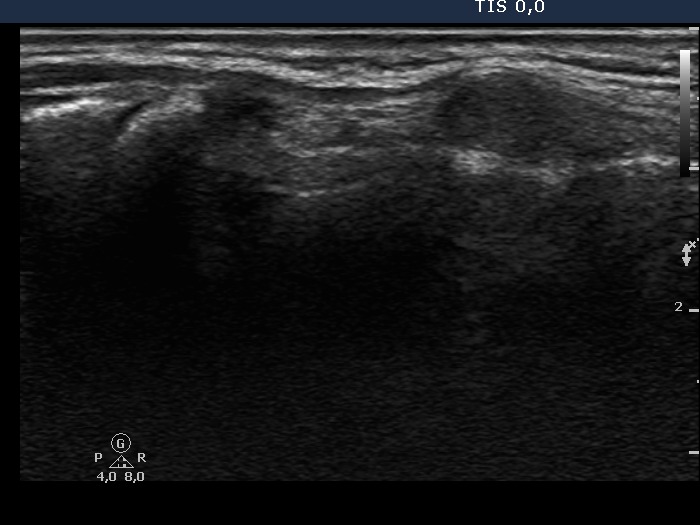

First examination - before surgery (first and second rows of images)

Ultrasonography. The right lobe was echonormal. There was a moderately hypoechogenic, inhomogeneous nodule with blurred borders in the left side of the isthmus. Another cystic nodule was present in the left thyroid.

Cytology of the solid nodule resulted in papillary cancer.